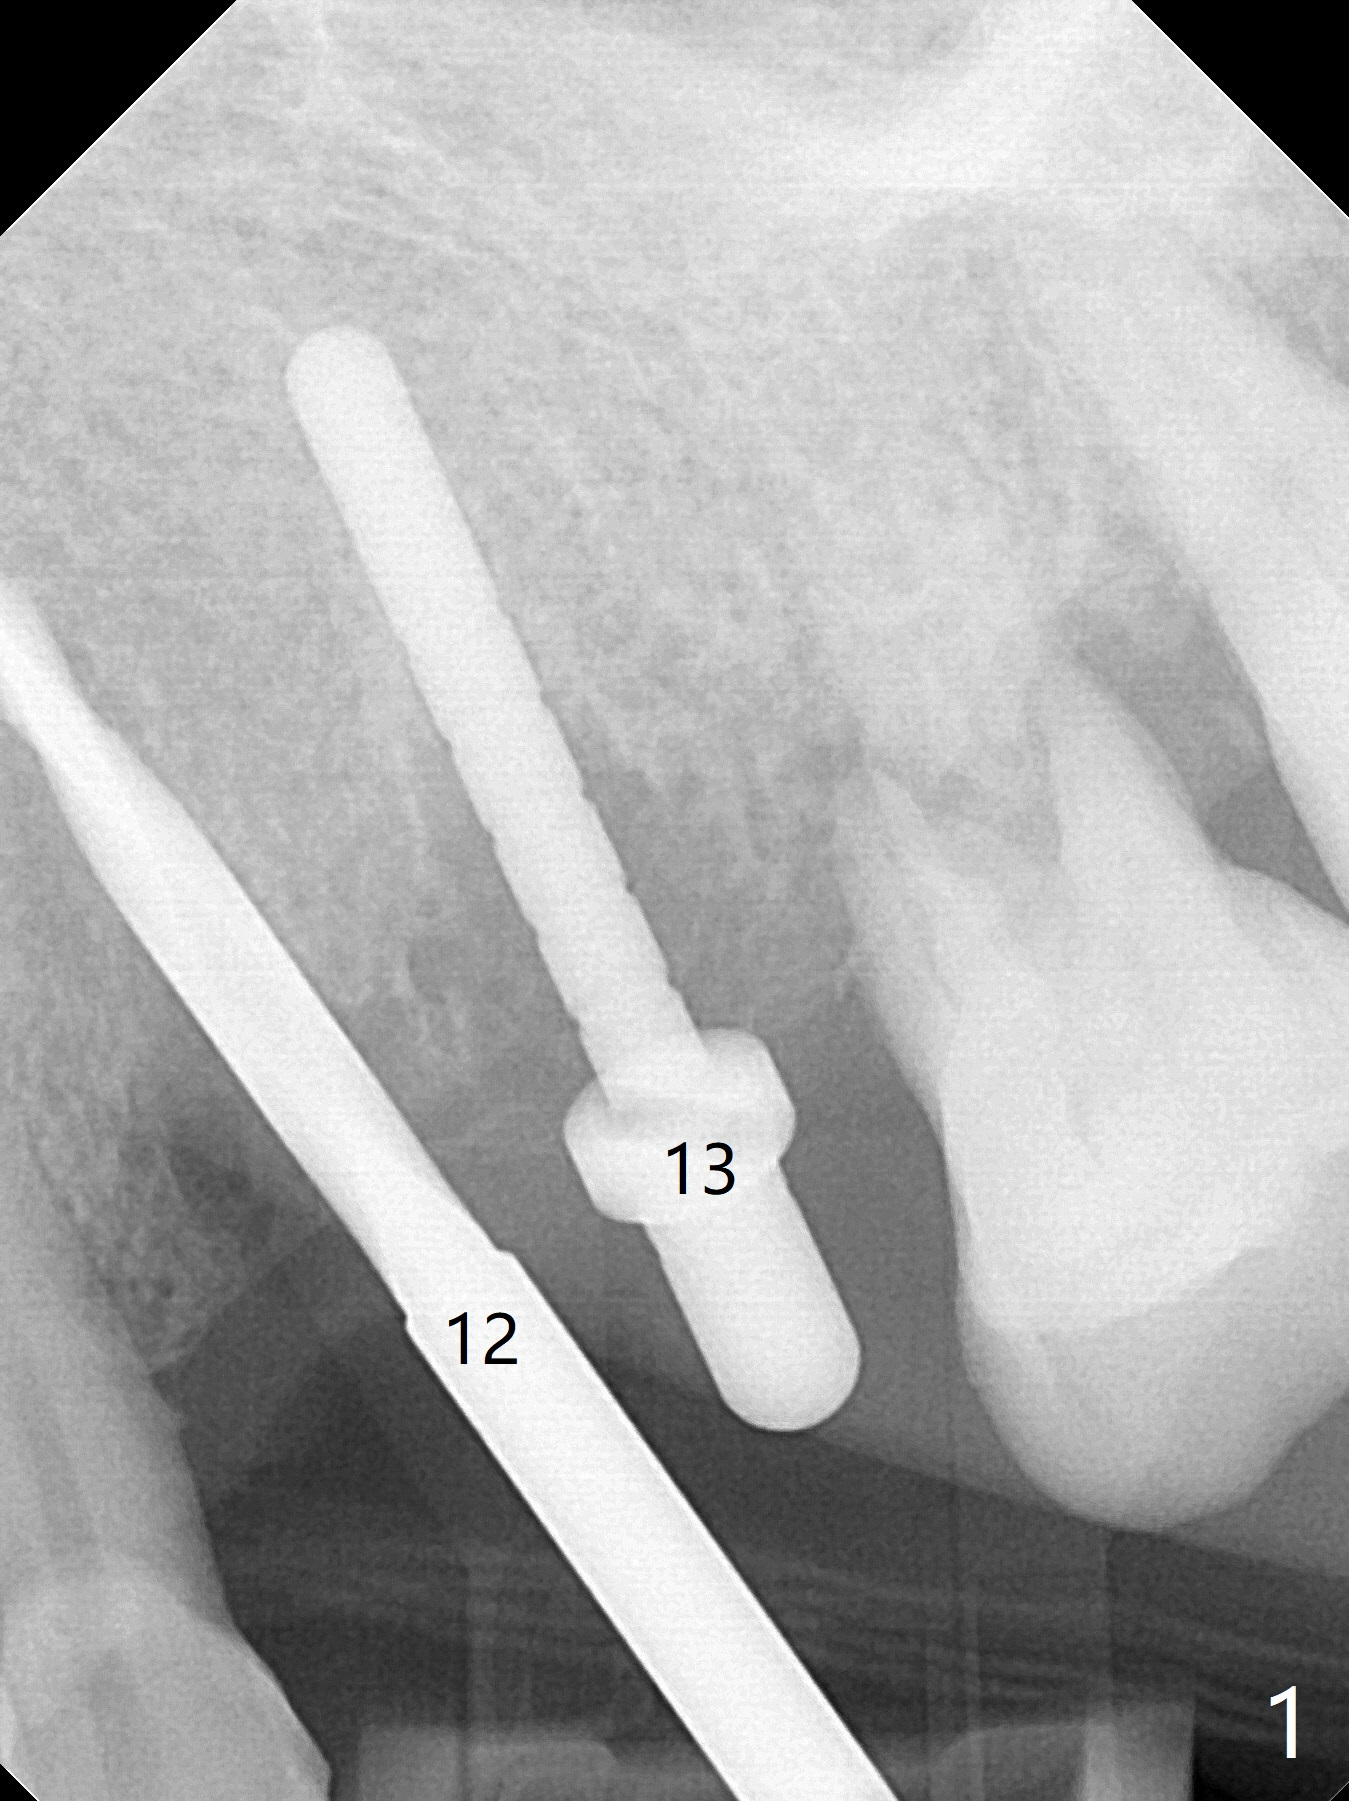

A 66-year-old woman returns to office requesting implant placement at #12 and 13 at an appointment supposed for #5 impression. Depth of osteotomy is 20 mm (gingival level, Fig.1 ( 2mm)). After correction of trajectory at #12 and 3 mm drill for 16 mm at the sites, two of 3.8x16 mm implant are placed with insertion torques of 35 and 15 Ncm, respectively (Fig.2). Before and after change into shorter abutments (4.5x4(4) and (5)), Vera Graft is placed (Fig.3 *). To increase stability, either increase the diameter (4 (Fig.4 at #5) or 4.5 mm instead of 3.8) or length of the implants (red dashed line: sinus floor). Or use dummy implants. The allograft appears to have been incorporated into the host bone nearly 4 months postop (Fig.5). The abutment of the isolate implant at #5 becomes loose twice (Fig.4). To reduce the chance of abutment loosening at #12 and 13, can you make splinted crowns? If the two separate crowns have been fabricated, can you make a slot (with light undercut) in the proximal area of each crown (Fig.6 (occlusal view): S) in addition to access hole (A)? After cementation, composite will be placed in the slots (lock) so that the crowns will not rotate and become loose.